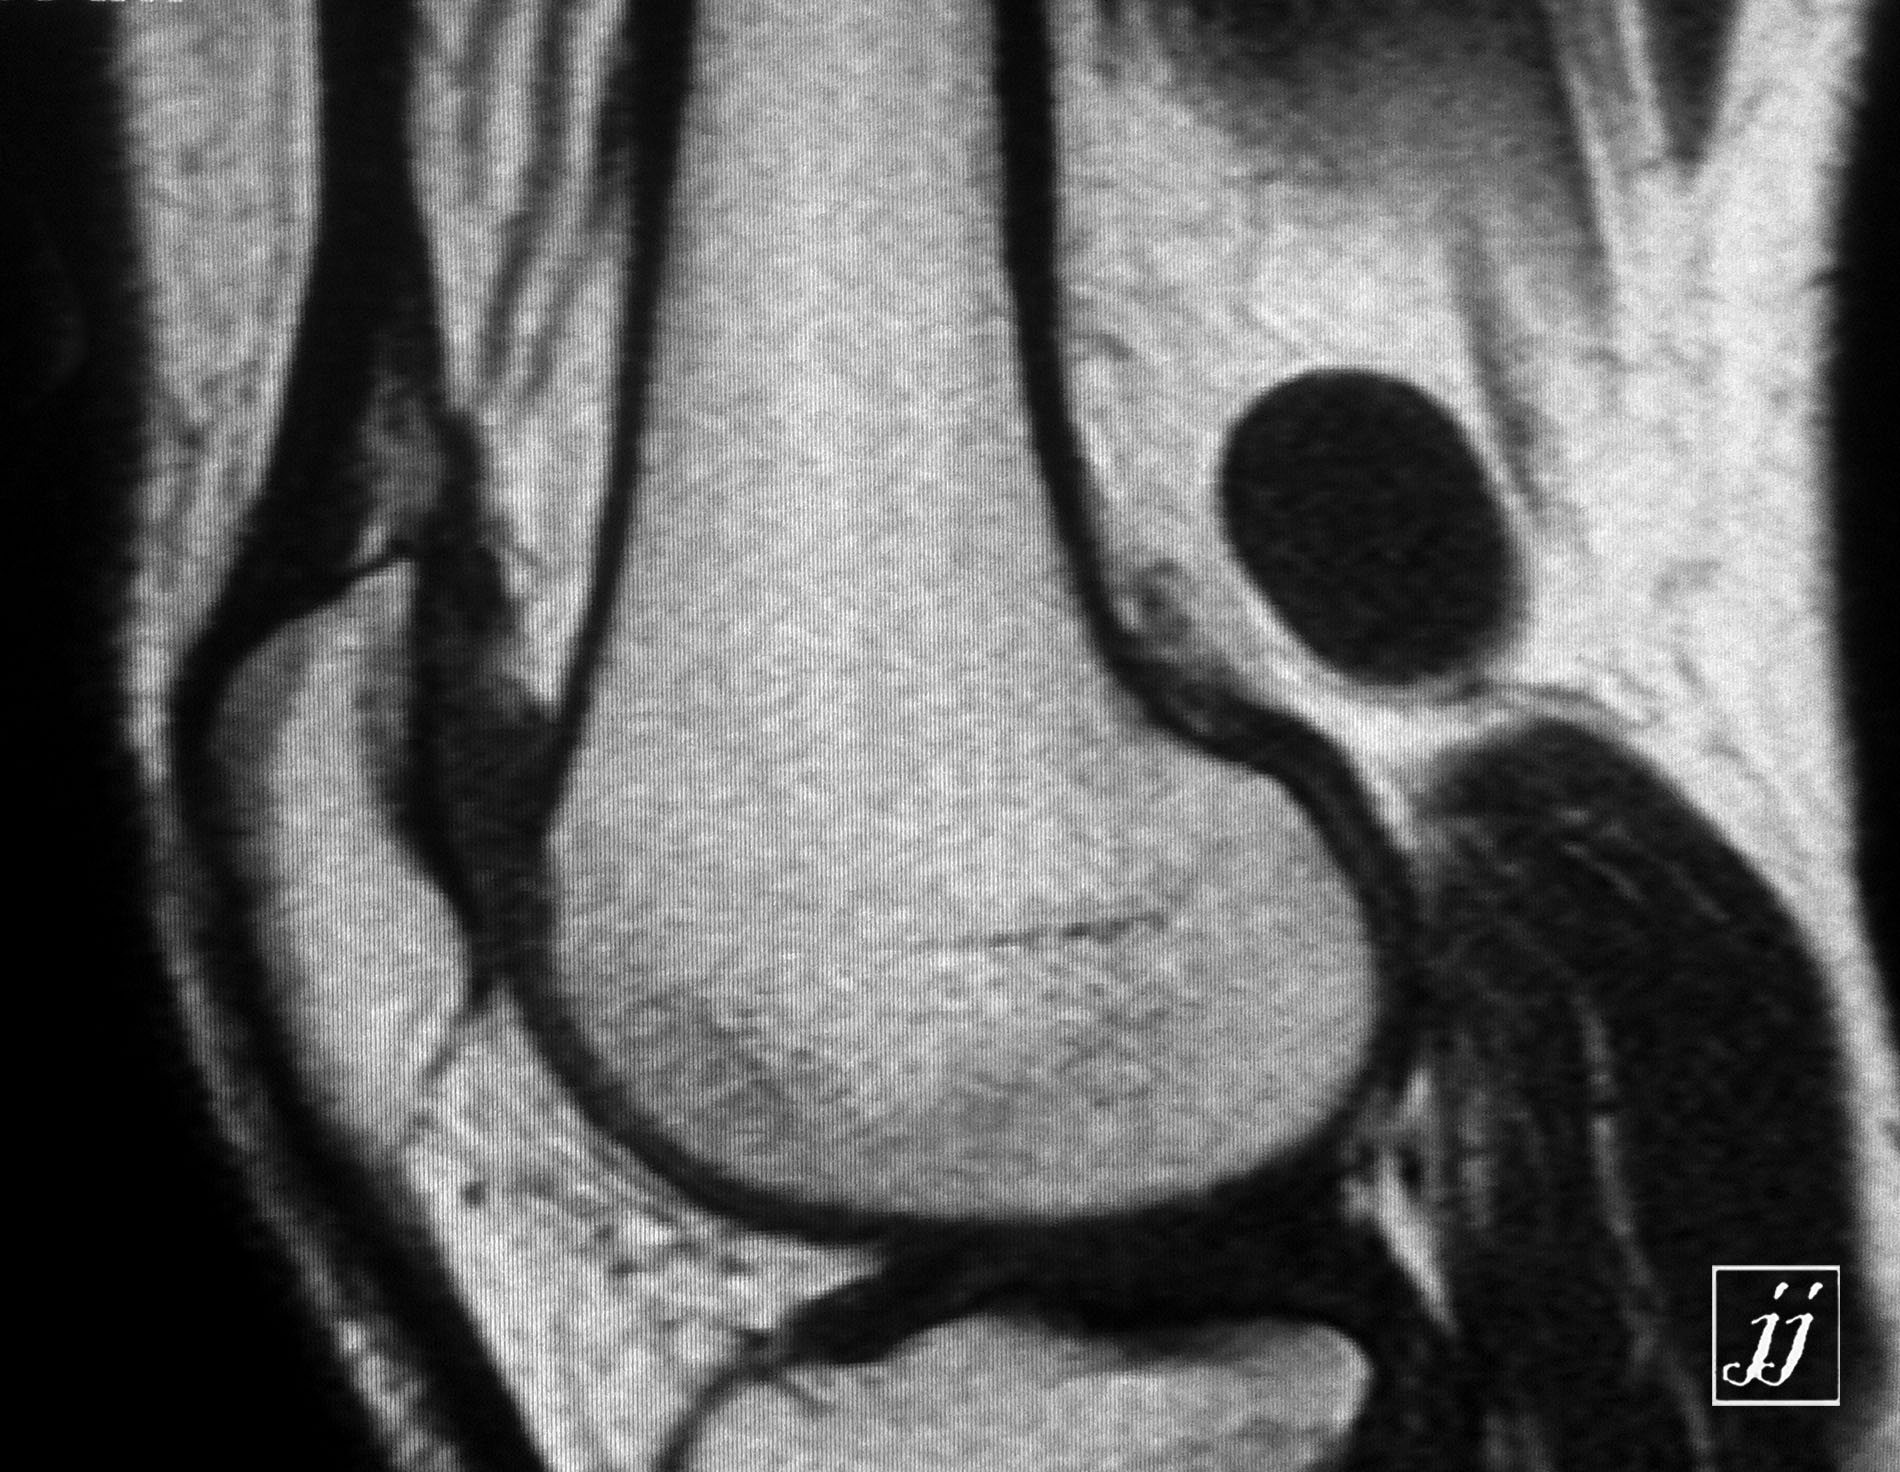

MSK- bi lateral popliteal cyst (7)